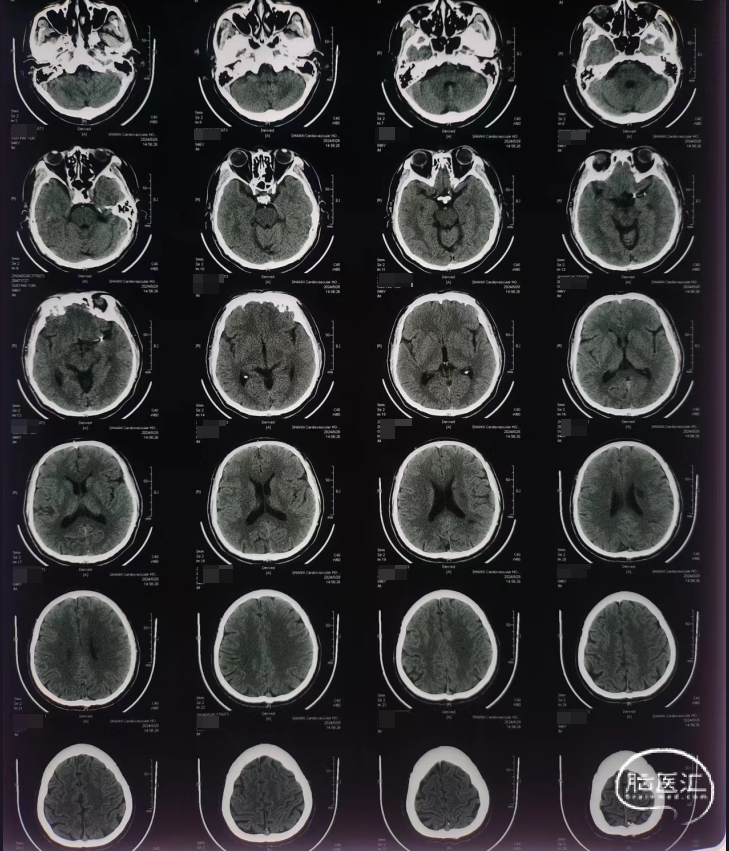

➢术前CTP

MTT

术后CTA复查。

术后复查头DWI及头CT:未见新发出血及新发脑梗死。

术后患者无头痛头晕,无语言及肢体活动障碍,NIHSS 0分。